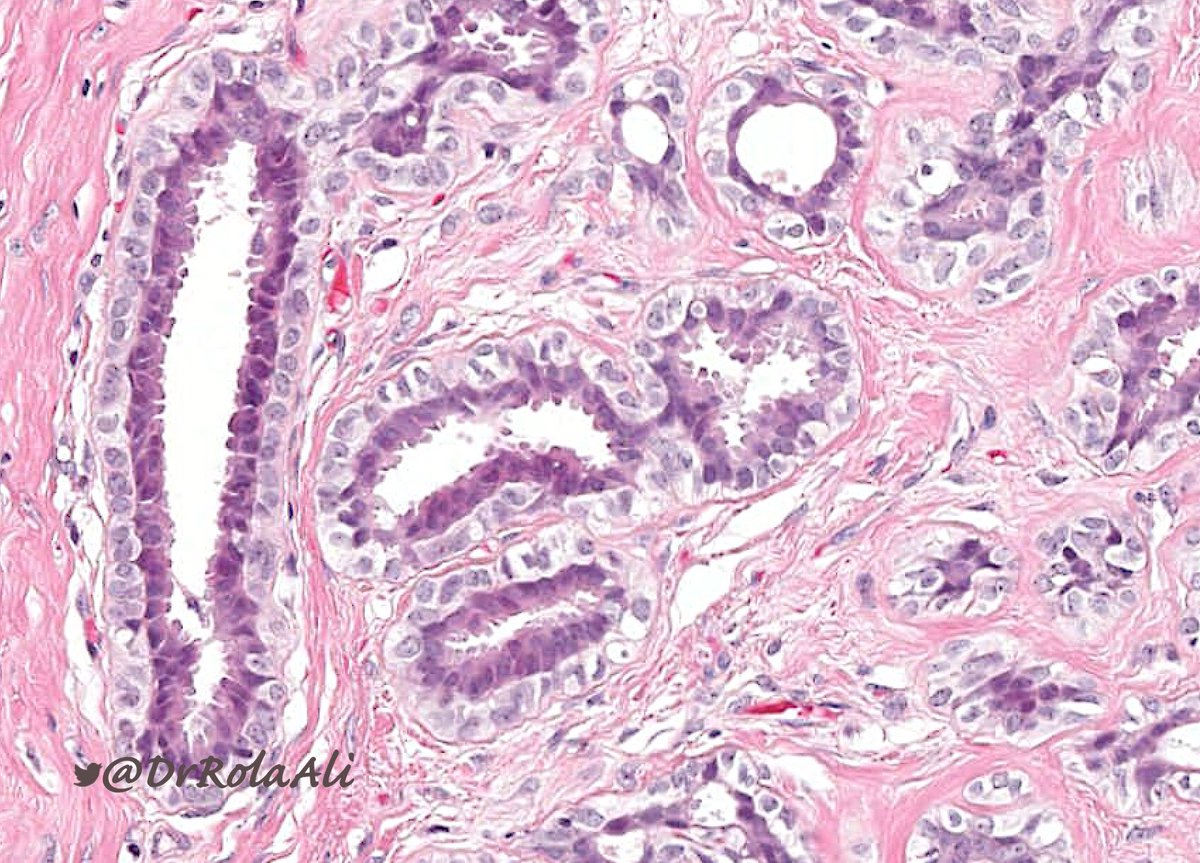

🔬 Adenomyoepithelioma

▪️Typically multinodular

▪️Biphasic

▪️Myoepithelial cells may be: polygonal and clear, spindle, myoid, plasmacytoid

▪️+/- accompanied by papillomatosis

▪️Benign